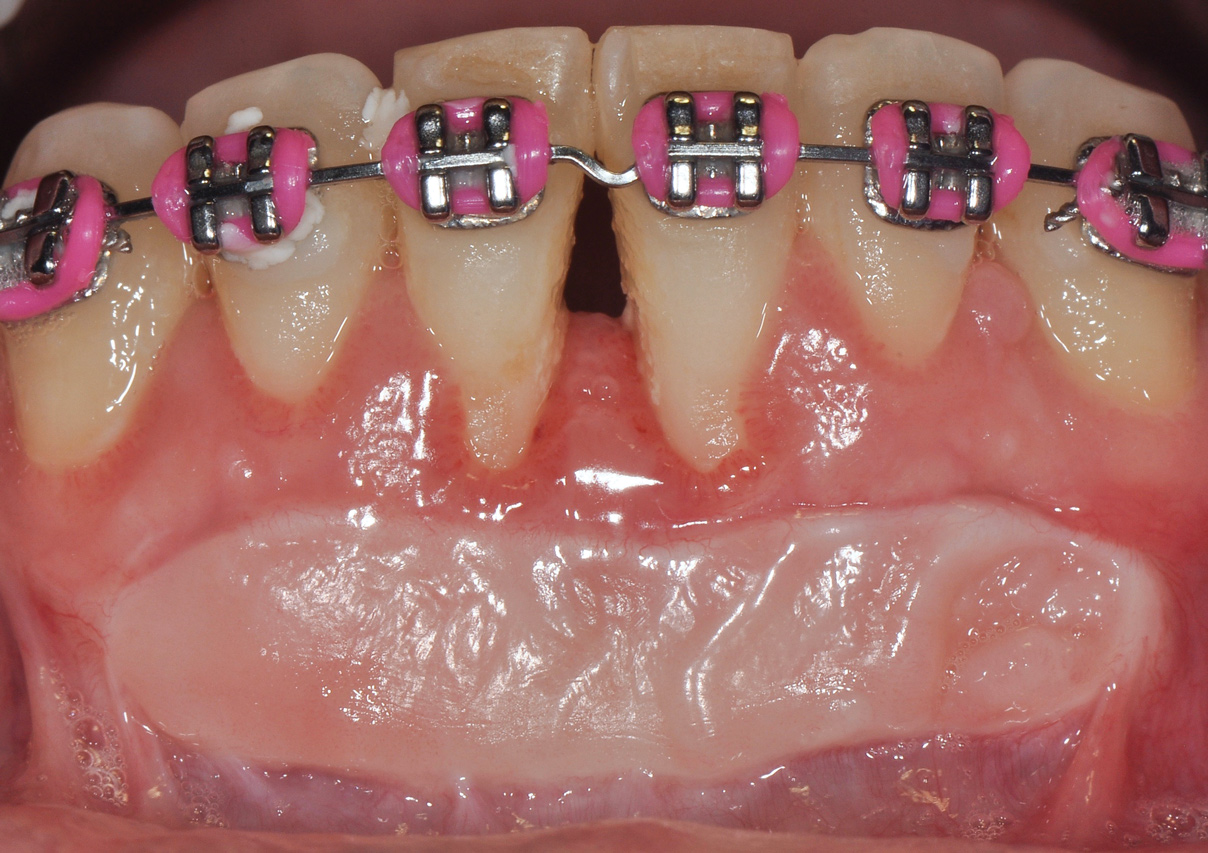

Although similar to the root coverage procedures mentioned above, gingival augmentation procedures not aimed at achieving root coverage are performed to facilitate plaque control, improve patient comfort, and prevent future periodontal recession. They may be used in conjunction with restorative, orthodontic, or prosthetic dentistry. The consensus report from the AAP's workshop group on soft-tissue non-root coverage procedures concluded that a specific minimum amount of keratinized tissue is not needed to prevent attachment loss when optimal plaque control is present; however, if plaque control is suboptimal, a minimum of 2 mm of keratinized tissue is needed.12 A standard procedure that is recognized to predictably gain keratinized tissue is the use of an autogenous gingival graft.12 Figure 5 through Figure 8 demonstrate the healing progression of a patient with poor oral hygiene whose mucogingival defect was treated with a free gingival graft and L-PRF from the patient's own blood.

(5.) Pretreatment photo of patient with recession to be treated with a free gingival graft (harvested from the palate) and L-PRF.

Figure 5

(6.) Postoperative view of the graft donor site after 3 weeks.

Figure 6

(7.) Postoperative view of the graft recipient site after 3 weeks showing healing progress with poor oral hygiene.

Figure 7

(8.) Postoperative view of the graft recipient site after 6 months showing healing progress with poor oral hygiene.

Figure 8